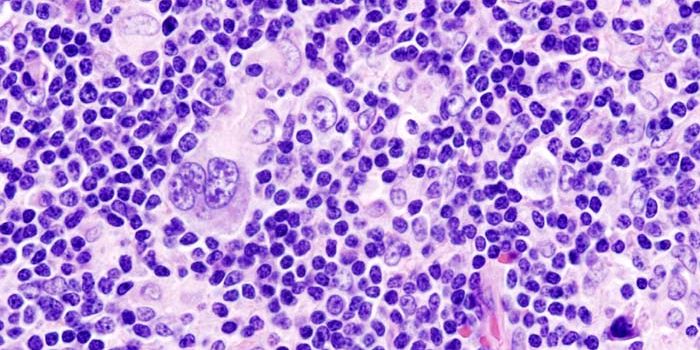

DEC 10, 2015ImmunologySuperior technology brings us novel images of cancer cells and lymphocytes this week, and now scientists can learn more ...